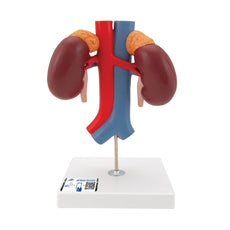

This Urinary System all-in-one-model shows:- Structures of retroperitoneal cavity

- Large and small pelvis with bones and muscles

- Inferior vena cava

- Aorta with its branches including iliacal vessels

- Upper urinary tract

- Rectum

- Kidney with adrenal gland.

One front half of a kidney is removable from the anatomical model of the urinary system. With easy to change male insert (bladder and prostate, front and rear half) and female insert (bladder, womb and ovaries, 2 lateral halves) the Urinary System model is a great teaching tool.

Dual Sex Urinary System model on baseboard.